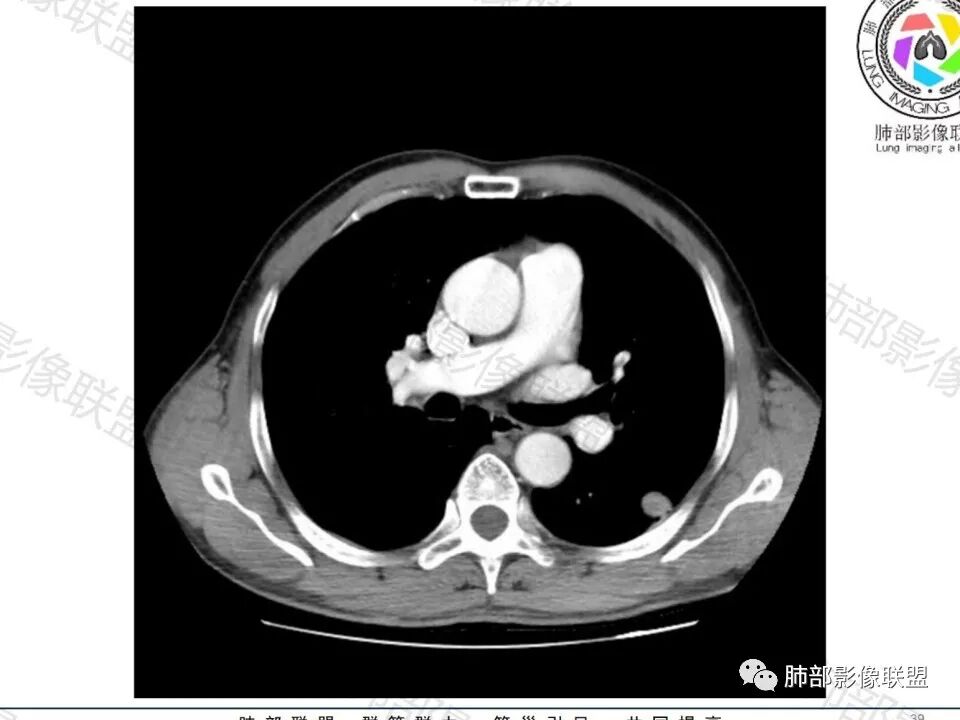

男,60体检发现左肺下叶结节,左肺下叶类圆形结节影,边界清晰,边缘见浅分叶及细短毛刺,病灶内见增粗血管影穿行,相应层面胸膜增厚,双肺另见微小结节影,增强扫描病灶轻度强化,考虑隐球菌,除外腺癌。

左肺下叶胸膜下实性小结节,边缘可见毛刺,轻度收缩,近端与血管束相连,远端轻度牵拉胸膜,并远端可见小空泡,平扫密度均匀,增强后渐近性强化,考虑腺癌,鉴别隐球菌

中老年男性患者,无症状体检发现,胸部CT:左下肺内前基底段近胸膜下类圆形结节,边缘清晰,周围晕征,周围毛刺细软,有胸膜牵拉及血管进入,增强扫描明显不均匀强化,考虑炎性肉芽肿,隐球菌可能,鉴别腺癌

左肺下叶背段结节,短毛刺实性血管集束,增强富血供,不管病理最后怎么样,日常写报告考虑恶性腺癌可能大,建议手术或抗炎后无变化也建议手术。

晨读:左肺下叶胸膜下实性小结节,边缘可见模糊晕及毛刺,轻度收缩,与支气管关系不清,近端与血管束相连,内见小空泡,平扫密度均匀,均匀强化。远近可见多个小结节。考虑炎性肉芽肿,隐球菌病,鉴别结核、腺癌。

类圆形,边缘稍平直,周围晕中细微毛刺,密度均匀,均匀强化,血管走形自然,稍牵拉扭曲,支气管在近端堵塞

这枚结节的纵隔窗在没有调节窗位的情况下,已经很密实了,说明这个结节里面是软组织的成分,这与普通炎性结节(隐球菌等)的密度还是有区别的,很多年前就有人提出,纵隔窗显示越大,恶性可能越大;

增强的程度很难讲,但是不均匀强化是可以确定的;